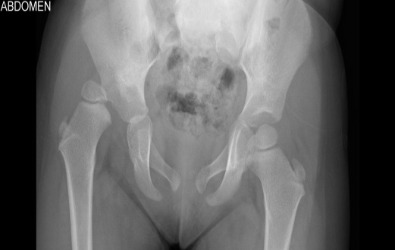

Προ-εγχειρητικά

Οι ακτινογραφίες απεικονίζουν περιστατικά με αναπτυξιακή δυσπλασία στα ισχία, τα οποία παρουσιάστηκαν στην κλινική μας μετά την ηλικία των τριών ετών. Πραγματοποιήθηκε χειρουργική επέμβαση από τον Δρ. Ζένιο για ανάταξη των ισχίων με οστεοτομία λεκάνης και μηριαίου.